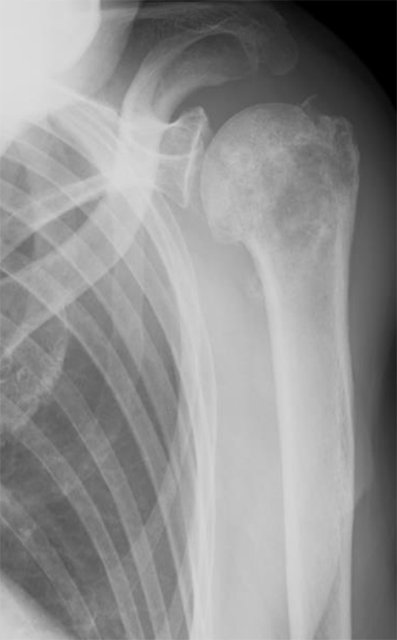

(3)腓骨移植

下腿にある腓骨と呼ばれる長管骨を採取し、移植します。骨と同時に皮膚も移植することができるため、骨欠損と軟部組織欠損を同時に治療することが可能です。また、血流のある骨移植であるため感染に対しても強く、感染性偽関節症例にも適応されます。

上腕骨腫瘍に対し、広範切除術と腓骨移植術を行った。